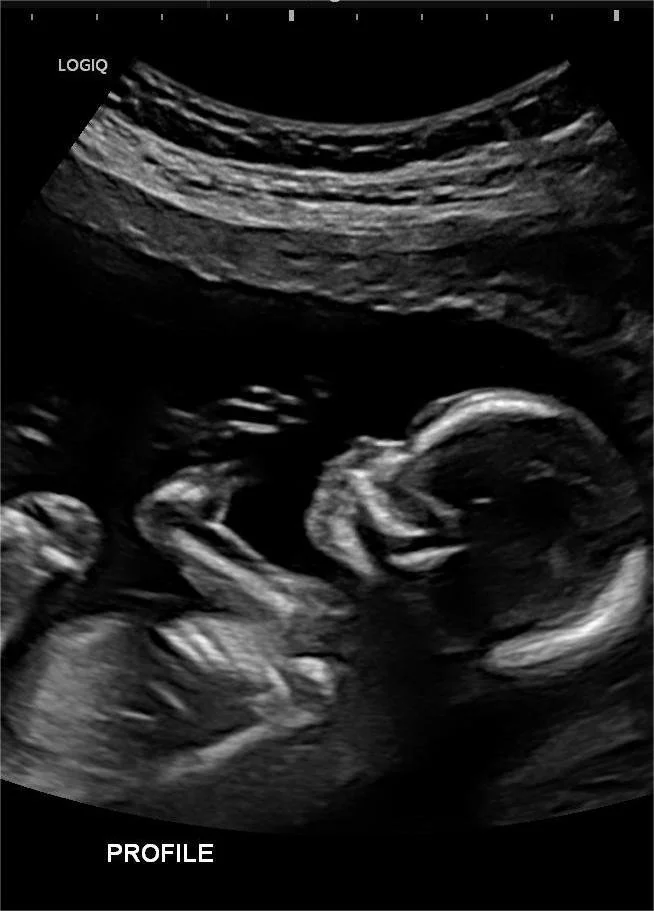

Obstetric and gynaecological ultrasound provides detailed imaging of the female pelvis and developing pregnancy. It is commonly used to monitor fetal growth and wellbeing, assess early pregnancy, and investigate gynaecological concerns such as pelvic pain or abnormal bleeding.

Obstetrics & Gynaecology

Dating Scan

Early Structural (12-16 Weeks) Scan*

Morphology*

Nuchal Translucency Scan*

Third Trimester